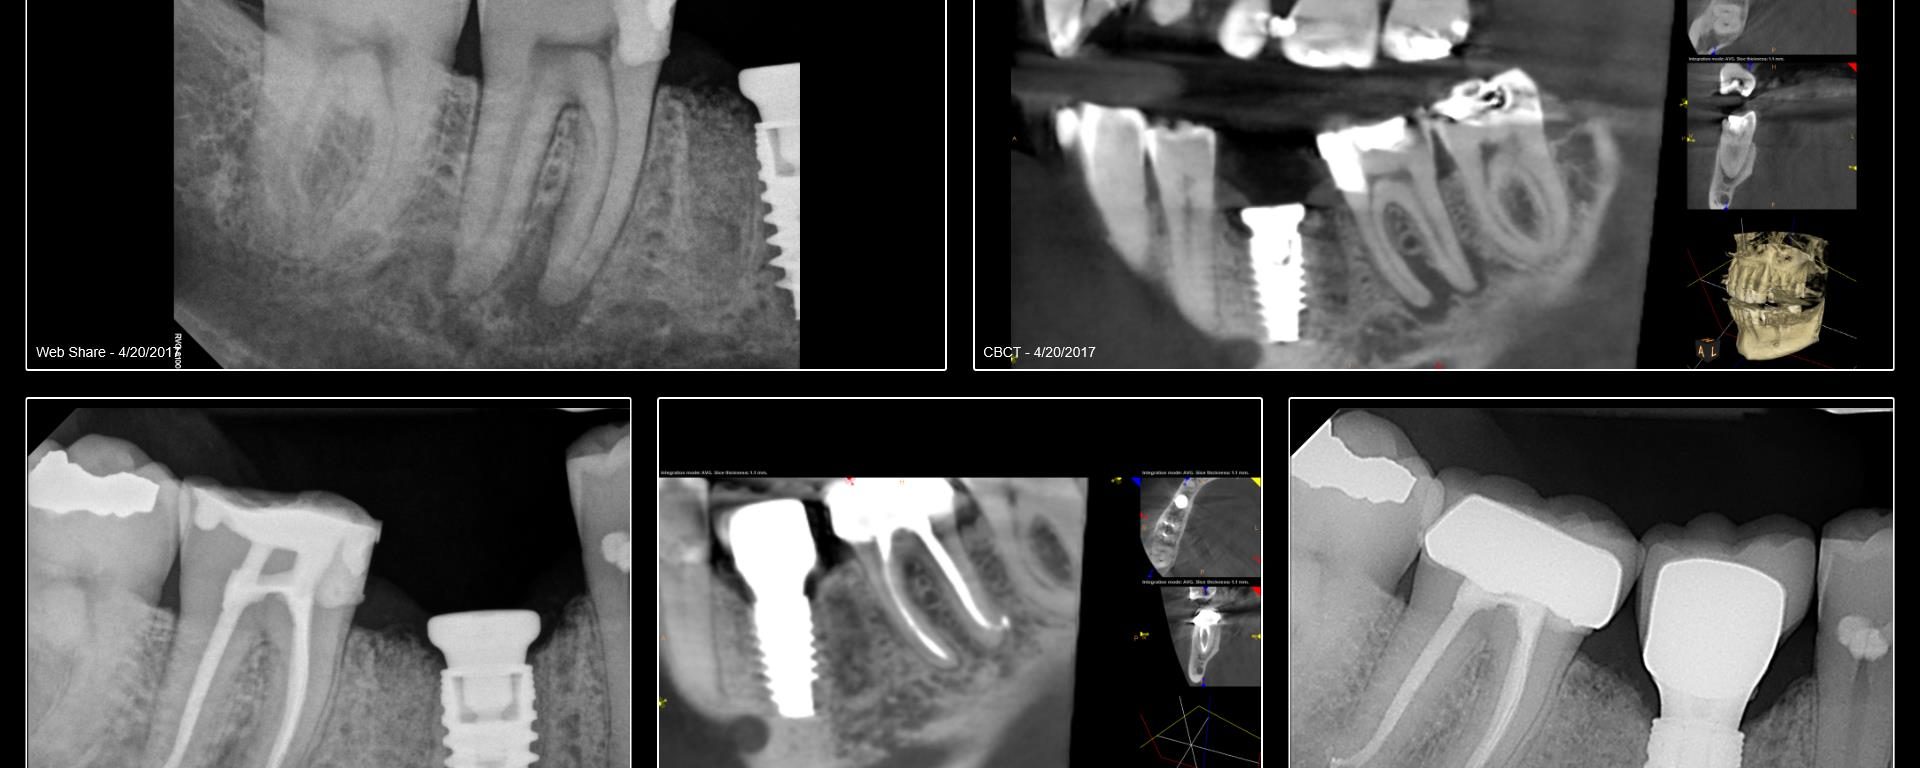

I began seeing this patient in 2014. Tooth #14 was diagnosed with a vertical root fracture at that time and the tooth was removed and the site grafted. He then presented in 2015 with a VRF of #15. It was removed and we discussed an implant in the #14 site. He did not follow up […]